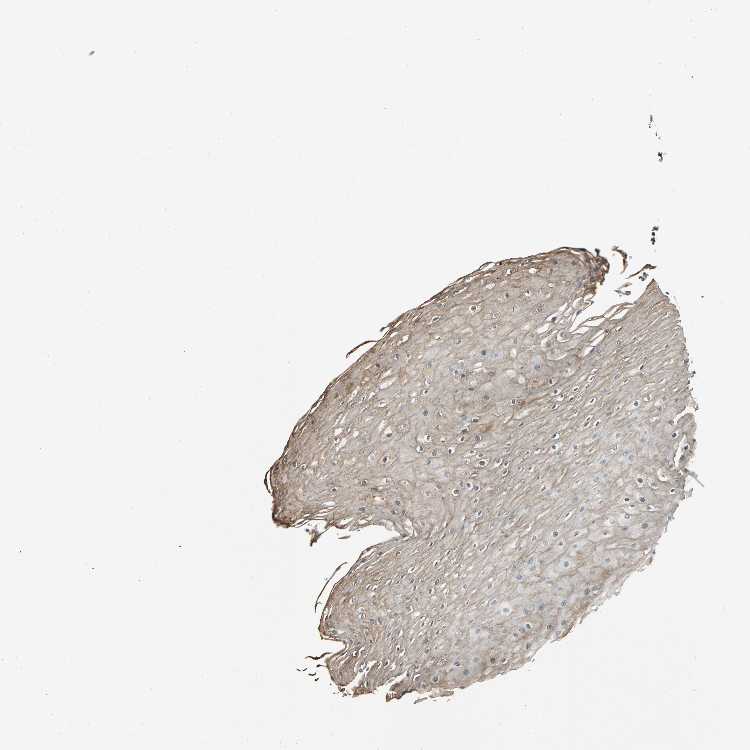

ESOPHAGUS - Antibody stainingi

Antibody staining in the annotated cell types in the current human tissue is reported as not detected, low, medium, or high, based on conventional immunohistochemistry profiling in selected tissues. This score is based on the combination of the staining intensity and fraction of stained cells.

Each image is clickable and will lead to virtual microscopy that enables deeper exploration of all samples and also displays staining intensity scores, fraction scores and subcellular localization as well as patient and tissue information for each sample.

Antibody HPA006616

Squamous epithelial cells Medium